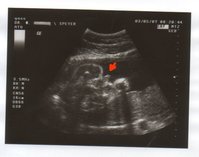

könnt ihr es erkennen?

Nachdem mein FA schon in der 16. Woche eine Vermutung äußerte, setze sich der Wurm seit dem in BEL, so dass man die ganze Zeit nichts mehr erkennen konnte.

Gestern war es dann in SL und hat sich von seiner besten Seite gezeigt.

Da hat wohl der FA recht behalten, trotz dass es in der 16. Woche noch so klein war.

Ansonsten ist alles in Ordnung. Mir und dem Baby geht es super.